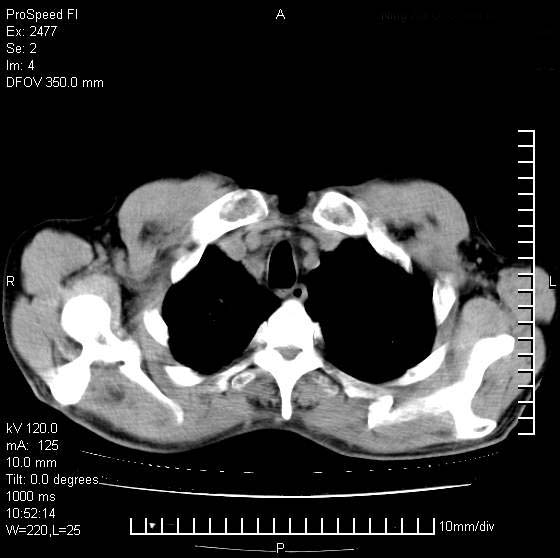

以下是引用天南地北在2007-10-9 14:29:00的发言:[br]1:右上肺结核[br]2:右肺下叶肿块:不支持肺癌,首先考虑炎性病变-肺脓疡可能性大[br]理由:1:临床病史支持,肺脓肿症状不明显应该是不规则服药造成。[br] 2:肿块边缘模糊,周围可见炎性渗出,长毛刺,内见支气管征,不过有点不规则。[br] 我感觉下肺癌这个诊断有点偏左,建议积极抗炎治疗后复查

以下是引用卜一在2007-10-9 15:55:00的发言:[br][br] [br] 1:右上肺结核[br]2:右肺下叶肿块:不支持肺癌,首先考虑炎性病变-肺脓疡可能性大[br]理由:1:临床病史支持,肺脓肿症状不明显应该是不规则服药造成。[br] 2:肿块边缘模糊,周围可见炎性渗出,长毛刺,内见空气支气管征,不过有点不规则。[br] 我感觉下肺癌这个诊断有点偏左,建议积极抗炎治疗后复查![br]支持! [br] [br] [br]

以下是引用wxy7406在2007-10-9 21:02:00的发言:[br]结合临床病史首先考虑感染性病变,但周围型肺癌不能除外,1.患者年龄偏大2.临床有咯血3.(也觉得是最重要的一点)病灶内有偏心性空洞。

以下是引用王仕学在2007-10-9 13:48:00的发言:[br]右下肺周围性肺癌可能性大,最好活检吧

以下是引用hhcckk在2007-10-9 15:18:00的发言:[br]右上肺病灶考虑结核,病灶多种形态并存(纤维化、增殖性病灶并存)[br]右下肺病灶比较难说,个人意见更趋向于“天南地北”的诊断----肺脓肿[br]1、病人有明显的寒战,高热,肿瘤病人很少出现[br]2、病灶周围的肺纹理走向柔和,没有肿瘤病灶常见的集束征[br]3、病灶边缘的毛刺较长,恶性肿瘤多为短毛刺[br]痰中血丝和病人的年龄是两个不利于良性肿块的因素,建议早点活检

以下是引用ydx_74在2007-10-9 15:53:00的发言:[br]右上肺结核,右下中心性肺癌可能大,肺门淋巴结肿大。